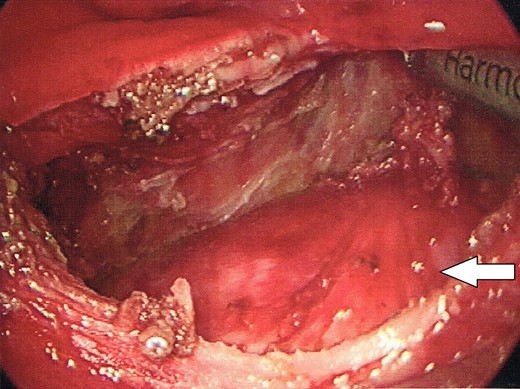

After insufflation, the contour of the retrorectal cyst could be seen distorting the posterior wall of the rectum. Using an Harmonic Scalpel (Ethicon, Johnson and Johnson), a longitudinal incision was made through the posterior midline of the rectal wall, overlying the presacral cyst (Fig. 3) in doing so, the avascular plane surrounding the cyst was able to be exposed.

Opening of the posterior wall of the rectum, into the posterior perirectal space.